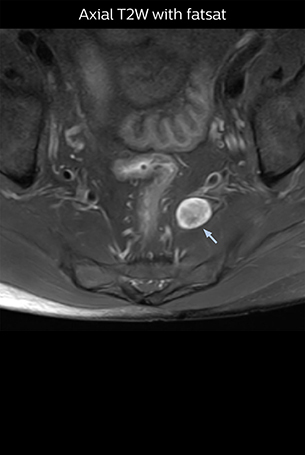

At Northern Fukushima Medical Center in Japan, excellent MRI visualization of nerves helps support confident diagnoses and informs surgical treatment decisions for patients with lower limb symptoms. MRI technologist Tanji and orthopedic surgeon Dr. Yabuki share how direct nerve visualization with the 3D NerveVIEW method adds information when diagnosing atypical herniations. The additional insights changed their way of working and benefit their patient care, as illustrated by some clinical examples.

“In patients with lower extremity neurological symptoms, NerveVIEW helps us to determine the disease matching the patient’s symptoms by directly visualizing the nerves. We use the sequence mainly, when there is suspicion of intraforaminal stenosis, extraforaminal stenosis or lateral disc herniation, which is often based on routine T2- and T1-weighted images. Additionally, the excellent depiction of the course of nerves makes NerveVIEW a good navigator when applying treatment such as block therapy or surgery.”

“Although symptoms of typical disc herniation and atypical hernia are very similar, the actual site of herniation is different. It is therefore important to characterize the nerve’s condition both inside and outside of the intervertebral foramina. “Conversely, if we see no abnormality in NerveVIEW, we can assume at least that there is no severe condition that requires surgery. Like this, it can help us avoid unnecessary surgery. NerveVIEW can have a tremendous impact in this way.”

“NerveVIEW is really useful for those cases where a nerve disorder is strongly suspected based on the clinical examination but our regular MRI images do not show any findings. These atypical herniations and spinal canal stenosis, occurring in 5% to 15% of the total lumbar herniation/stenosis cases are our main target when using NerveVIEW,” says Dr. Yabuki.